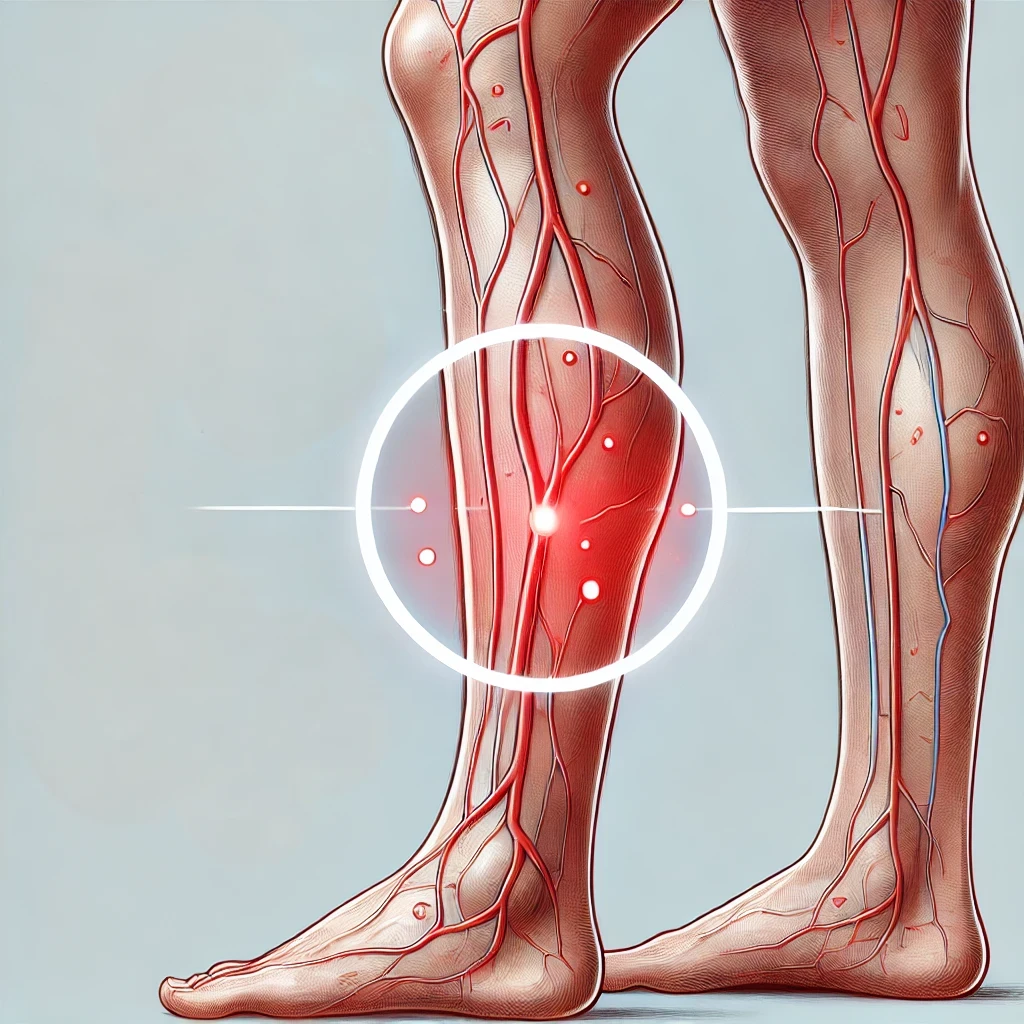

Sintomi della trombosi lieve

La trombosi lieve può manifestarsi con sintomi sfumati o lievi, spesso localizzati in aree come gli arti inferiori. I sintomi più comuni includono:

- Gonfiore localizzato nella gamba o nel braccio interessato.

- Dolore o senso di pesantezza, soprattutto in piedi o camminando.

- Arrossamento o colorazione bluastra della pelle nella zona colpita.

- Calore nella zona interessata, causato dall’infiammazione.

- Vene più visibili o dilatate.